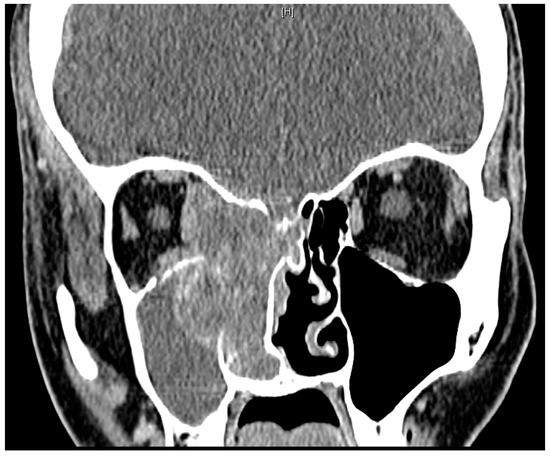

CT Neck/Sinus demonstrated a large, enhancing mass in the right nasal cavity measuring 5.9 cm × 3.7 cm × 5.3 cm, which involved the entire right ethmoid sinuses and right maxillary sinus with post-obstructive opacification of the right frontal and sphenoid sinuses (Figure 2). There was also extension into the right orbit, with mass effect on the medial rectus and optic nerve as well extension into the right anterior cranial fossa. Multiple enlarged retropharyngeal, supraclavicular, and mediastinal lymph nodes were also identified (Figure 3). Magnetic resonance imaging (MRI) of the brain was significant for mass extension 4 mm into the right anterior cranial fossa. CT Chest, Abdomen, and Pelvis were notable for a large right breast mass as well as metastatic disease in the hilum, chest wall, lungs, liver, pancreas, peritoneal cavity, and right ovary.

Figure 2. CT Sinus with Contrast on presentation to our hospital, coronal view. Large, heterogeneously enhancing mass of the right nasal cavity with post-obstructive opacificaiton of the right maxillary sinus. Bony destruction of the right lamina paprycea and cribiform plate.